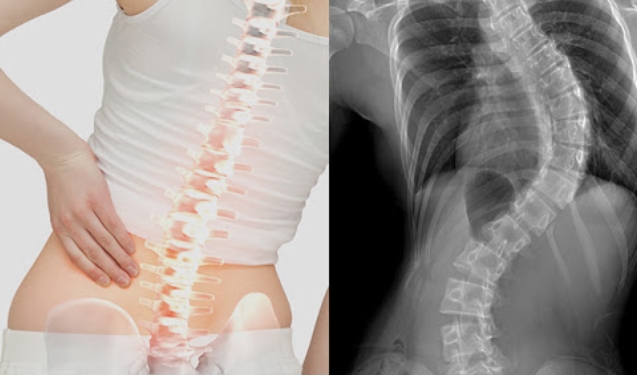

척추측만증은 척추가 휘어져 몸의 균형이 틀어진것을 말합니다.

통증과 함께 심폐기능 이상을 유발할 수 있습니다. 대표적인 치료방법은 척추측만증 교정운동입니다.